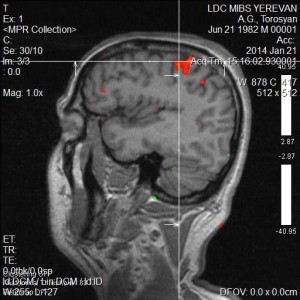

Նկարներում պատկերված է ձախ ձեռքի շարժիչ կենտրոնը, այն գտնվում է աջ կիսագնդի առաջկենտրոնական գալարում:

Ֆունկցիոնալ ՄՌՏ գնահատում է ուղեղի նեյրոնալ ակտիվության հետևանքով առաջացած հեմոդինամիկ փոփոխությունները, որի շնորհիվ հնարավոր է դառնում մեծ ճշգրտությամբ առանձնացնել ուղեղի կենտրոնները (խոսքի, տեսողության, շարժիչ և այլն): Չխորանալով մեթոդի ֆիզիկական սկզբունքների մեջ նշենք, որ ֆՄՌՏ-ի շնորհիվ կարելի է խուսափել կամ գոնե կանխատեսել հետվիրահատական նյարդաբանական դեֆիցիտները: Նախկինում նույնիսկ ամենաշնորհալի նյարդավիրաբույժները չէին կարողանում պատասխանել հիվանդների հարցերին, կապված հետվիրահատական բարդությունների հետ: Դա առաջին հերթին պայմանավորված է անատոմիական յուրահատկություններով, հարկ է նշել, որ պացիենտների գլխուղեղի ֆունկցիոնալ զոնաները լրջորեն կարող են տարբերվել բժշկական համալսարաններում օգտագործվող անատոմիական ատլասներում ներկայացված գլխուղեղի զոնաներից: Հետևաբար վիրաբույժի աչքի համար անտեսանելի կենտրոնները շատ հաճախ վնասվում էին և վիրահատությունից հետո պացիենտները դժվարանում էին ինքնուրույն տեղաշարժվել, կորցնում էին ինքնասպասարկման տարրական ունակությունները, խոսքի կարողությունը: